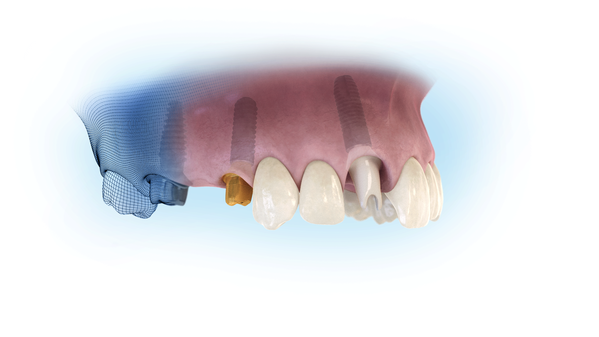

Gli impianti endossei rappresentano oggi uno strumento valido e affidabile per sostituire un singolo dente, più denti o arcate complete. Si tratta di “radici” in titanio che vengono inserite nell’osso, dove si sono persi o mancano denti e sulle quali si posizionano corone singole, ponti o protesi totali.

In questo modo possono essere evitate sedute molto invasive e lunghe per il paziente e se ci sono le condizioni, è possibile avere i denti in bocca già nelle 24 ore successive all’intervento.

In questo modo possono essere evitate sedute molto invasive e lunghe per il paziente e se ci sono le condizioni, è possibile avere i denti in bocca già nelle 24 ore successive all’intervento.